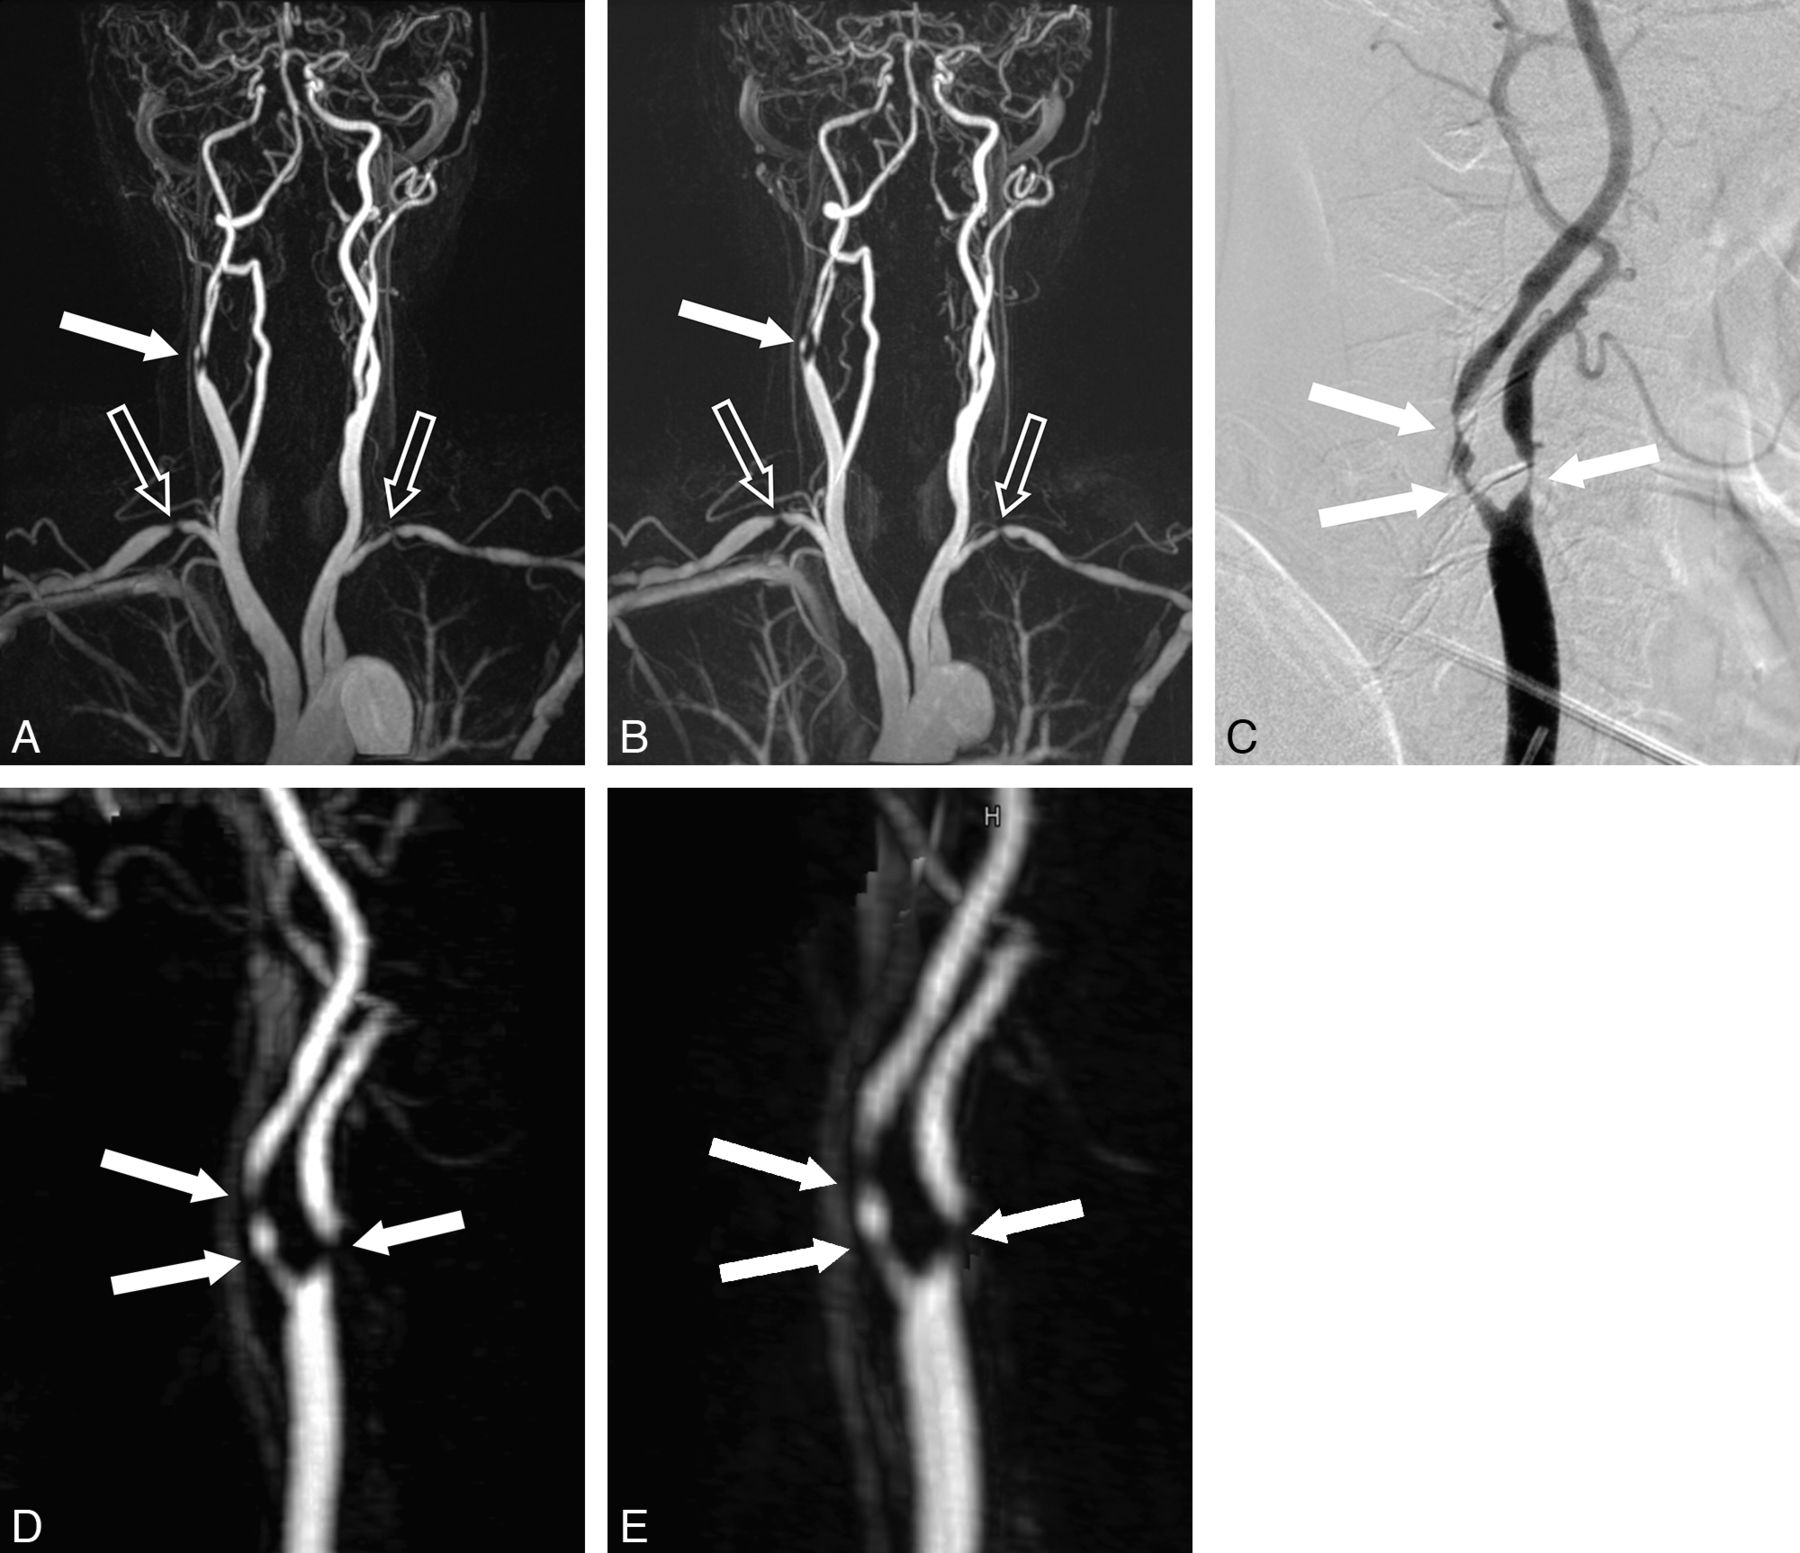

The diagnostic performance of CE-MRA for the detection of hemodynamically relevant stenosis is summarized in the On-line Table. Consistently superior performance was noted for gadobenate dimeglumine relative to gadopentetate dimeglumine, with significant superiority noted by reader 2 for determinations of accuracy (95.8% versus 92.4%, P = .016) and PPV (85.2% versus 73.7%, P = .008). Examples of the comparable quality and diagnostic efficacy achieved with 0.1-mmol/kg gadobenate dimeglumine and 0.2-mmol/kg gadopentetate dimeglumine are shown in Figs 2 and 3.

A 72-year-old male patient referred for MR imaging to guide revascularization of symptomatic carotid artery stenosis. The MIP image (A) acquired after 0.1-mmol/kg gadobenate dimeglumine (8 mL injected at 0.8 mL/s) reveals severe stenosis in both the left and right subclavian arteries (open arrows) and a ≥60% stenosis (closed arrow) of the right carotid bifurcation/ICA. Similar findings are seen on the analogous MIP image (B) acquired after 0.2-mmol/kg gadopentetate dimeglumine (16 mL injected at 1.6 mL/s). Selective DSA of the right carotid bifurcation/ICA (C) confirms the findings of the CE-MRA examinations after gadobenate dimeglumine (D) and gadopentetate dimeglumine (E). Note the sharper vessel delineation and greater contrast enhancement achieved with gadobenate dimeglumine.